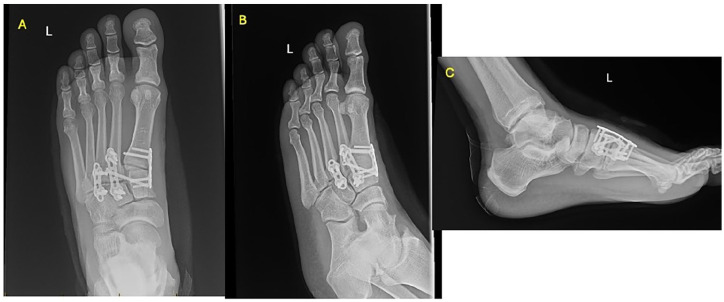

Abstract Image